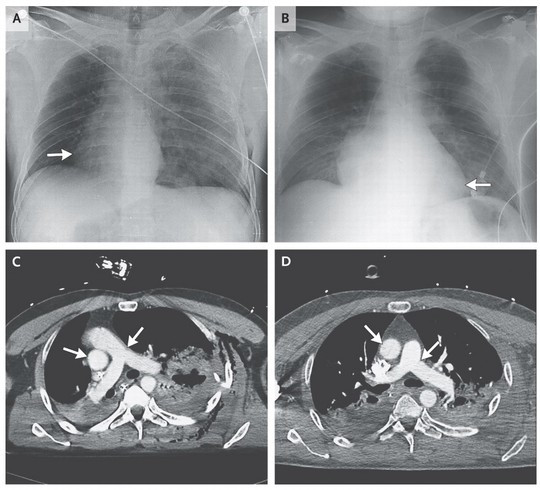

Nhóm bác sĩ cấp cứu người bị nạn phát hiện rằng trái tim của bệnh nhân đã dịch chuyển khi họ tìm cách nghe nhịp tim. Xét nghiệm hình ảnh cho thấy tim bệnh nhân đã xoay chuyển 90 độ về bên phải. Nhóm thầy thuốc này mô tả trường hợp hiếm có này trên tờ New England Journal of Medicine, hôm 7-5.

Tim bệnh nhân xoay 90 độ sau tai nạn

Nhóm bác sĩ điều trị phát hiện các vết thương ở phổi bệnh nhân và tai nạn khiến khí trong phổi thoát ra ngoài, đẩy trái tim về bên phải. Sau khi họ rút khí khỏi lồng ngực, tim bệnh nhân lại xoay về bên trái và trở lại vị trí cũ sau 24 giờ.